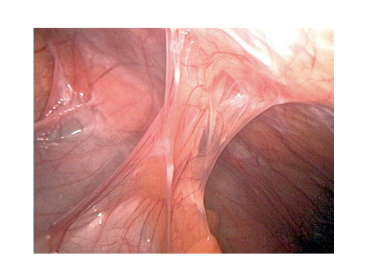

- Trước đây, mổ mở đã được coi là PT tiêu chuẩn cho tắc ruột do dính.

- PTNS: Ít nguy cơ dính, sớm có nhu động ruột, giảm đau tốt và thời gian nằm viện ngắn

- PTNS trong các trường hợp ruột giãn nhiều, dính phức tạp có thể làm tăng nguy cơ thủng ruột. Một số tác giả đã báo cáo tổn thương ruột ở 6,3-26,9%. Tỷ lệ cắt ruột 53,5% so với 43,4% mổ mở.

- PTNS điều trị dính ruột cũng khó khăn hơn ở những BN đã xạ trị

- PTNS cần lựa chọn chỉ định.

- PTNS thường áp dụng ở BN tắc ruột sớm hoặc thể trạng tốt

- Các yếu tố tiên lượng để PTNS thành công:- ≤2 lần tiền sử mổ mở,

- Cắt ruột thừa,

- Không có vết mổ cũ đường trắng giữa, và

- Chỉ một lần dính ruột duy nhất